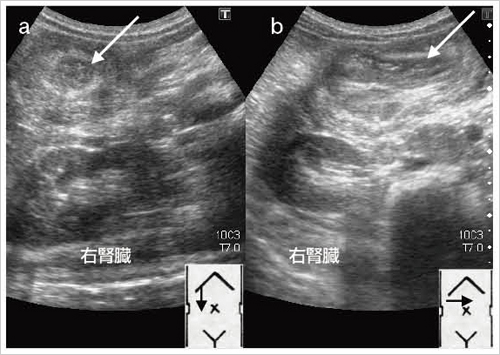

消化管エコーの診かた・考え方第2版

医学書院

2004/04/01

4260106546

9784260106542

消化管エコーの診かた・考え方第2版

医学書院

2004/04/01

4260106546

9784260106542